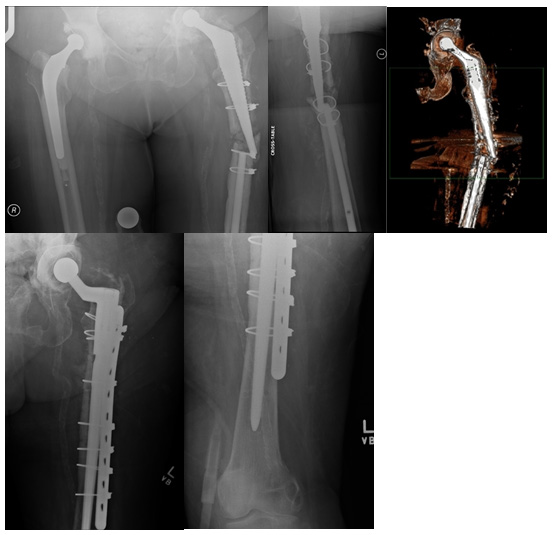

1. Radiograph- sufficient to arrive at the diagnosis in this case (Figure 1)

Figure 1 Pre-operative (above) and post-operative (below) images.

2. Satisfactory post-operative radiographs- fracture union seen (Figure 1)